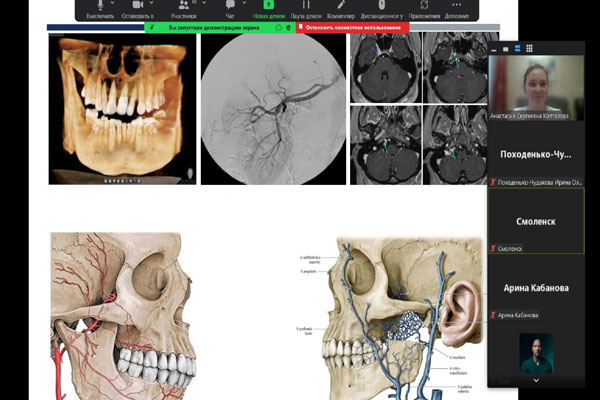

ВОЗМОЖНЫЕ СТОМАТОЛОГИЧЕСКИЕ ПОСЛЕДСТВИЯ КОВИДА

Кафедра хирургической стоматологии и челюстно-лицевой хирургии с курсом лор-болезней совместно с представителями дружественных университетов провела общее заседание студенческих научных кружков из четырех вузов. Общение проходило в дистанционном формате и объединило будущих медиков Рязани, Воронежа и Смоленска, а также представителей Белоруссии из Витебска.